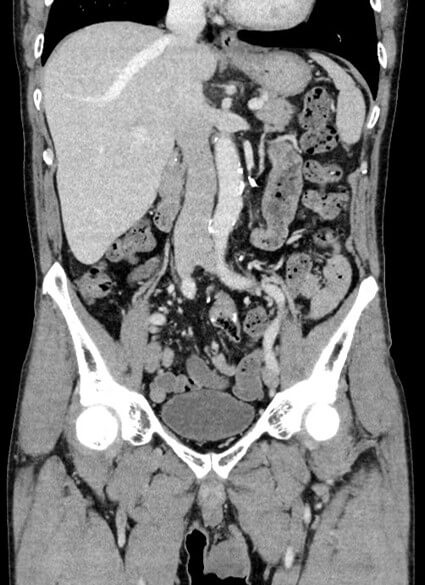

DECT

Dual Energy CT(DECT)は、2種類のX線エネルギーデータを取得し画像を構成する技術です。この技術により造影検査で用いる造影剤量の低減、金属による画質低下を抑えることが可能になりました。またこの同技術では、エネルギーの違いによるCT値の変化から組織形成が推測可能となるため、腫瘍や組織成分の鑑別にも期待できます。